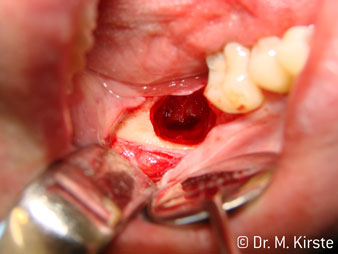

Le contre-angle avec tête angulée à 45° a surtout été choisi pour ses nombreux avantages. Les collègues qui exercent en chirurgie, et à qui cet instrument est principalement destiné, apprécieront très vite la possibilité de travailler efficacement dans des zones très étroites. En particulier, lors d’extractions de dent de sagesse (Ill. 2), où il n'y a pas besoin d’un grand angle d’écartement des tissus mous dans la région de la joue (Ill. 3). Pendant la préparation, une légère rotation de la tête de l’instrument permet un travail rapide et sans risque dans la zone rétromolaire.

En terme de rapidité, l'instrument peut atteindre jusqu’à 100 000 tr/min. Tandis qu'un spray très professionnel et une tête aux dimensions réduites répondent à toutes les exigences en matière de refroidissement et de visibilité de la zone de traitement.

La conception particulière des roulements à l'intérieur de la tête du contre-angle garantit un fonctionnement silencieux de l’instrument rotatif et lui procure une grande efficacité de coupe, sans à-coup ; ce qui est appréciable lors des interventions chirurgicales comme par exemple les séparations dentaires et résections apicales (Ill. 4-9).